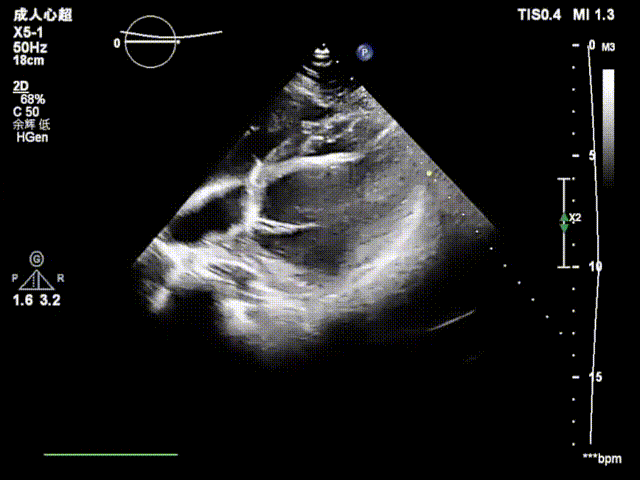

患者为41岁女性,存在金属过敏,既往偏头痛6年,头颅核磁提示存在多发脑缺血灶,右心声学造影提示心房水平大量右向左分流,符合PFO封堵指征。手术在单纯经胸超声指导下开展,术中操作较为顺畅,从建立工作路径到封堵器释放完成,整体手术仅耗时15分钟。术中经导管将28 mm×28 mm MemoSorb®可降解PFO封堵器精准送达卵圆孔未闭处后,在超声指导下严格遵循规范化5S操作步骤,先释放左盘面,牵拉成型线让左盘成型并贴壁稳定,继续回撤鞘管释放右盘面,超声下确认封堵器位置骑跨于缺损两侧、形态良好后,再次牵拉成型线。

上:左盘释放成型;下:右盘释放成型

锁定封堵器并使其完全成型后,释放封堵器,复查超声示封堵器紧贴房间隔,夹合牢靠,无残余分流!

术后超声